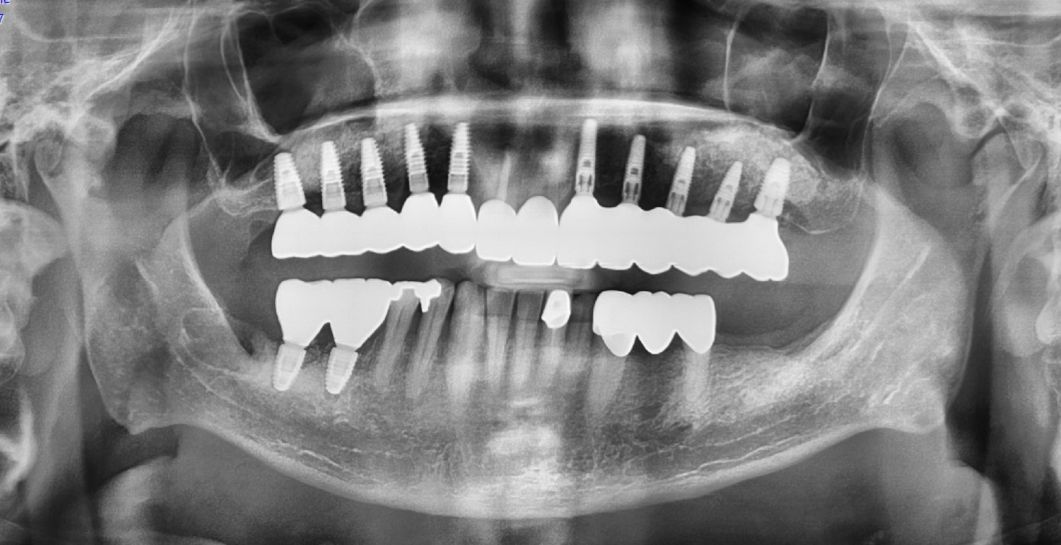

The answer is a resounding YES! It’s technically possible, but it’s also very easy to be exposed by radiographs or a CT scan. Doing so would have put that spy dentist at great risk. I would not wanna be that person.